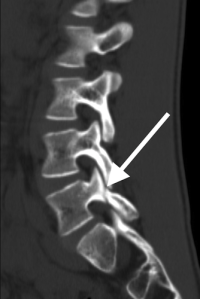

(Click to Enlarge Image) This is a CT scan of the side view of the lumbar spine in a patient with isthmic spondylolisthesis. The black arrow points to an intact pars (the bony area that connects the upper and lower facets). The white arrow points to the fracture and separation of the upper and lower facets.